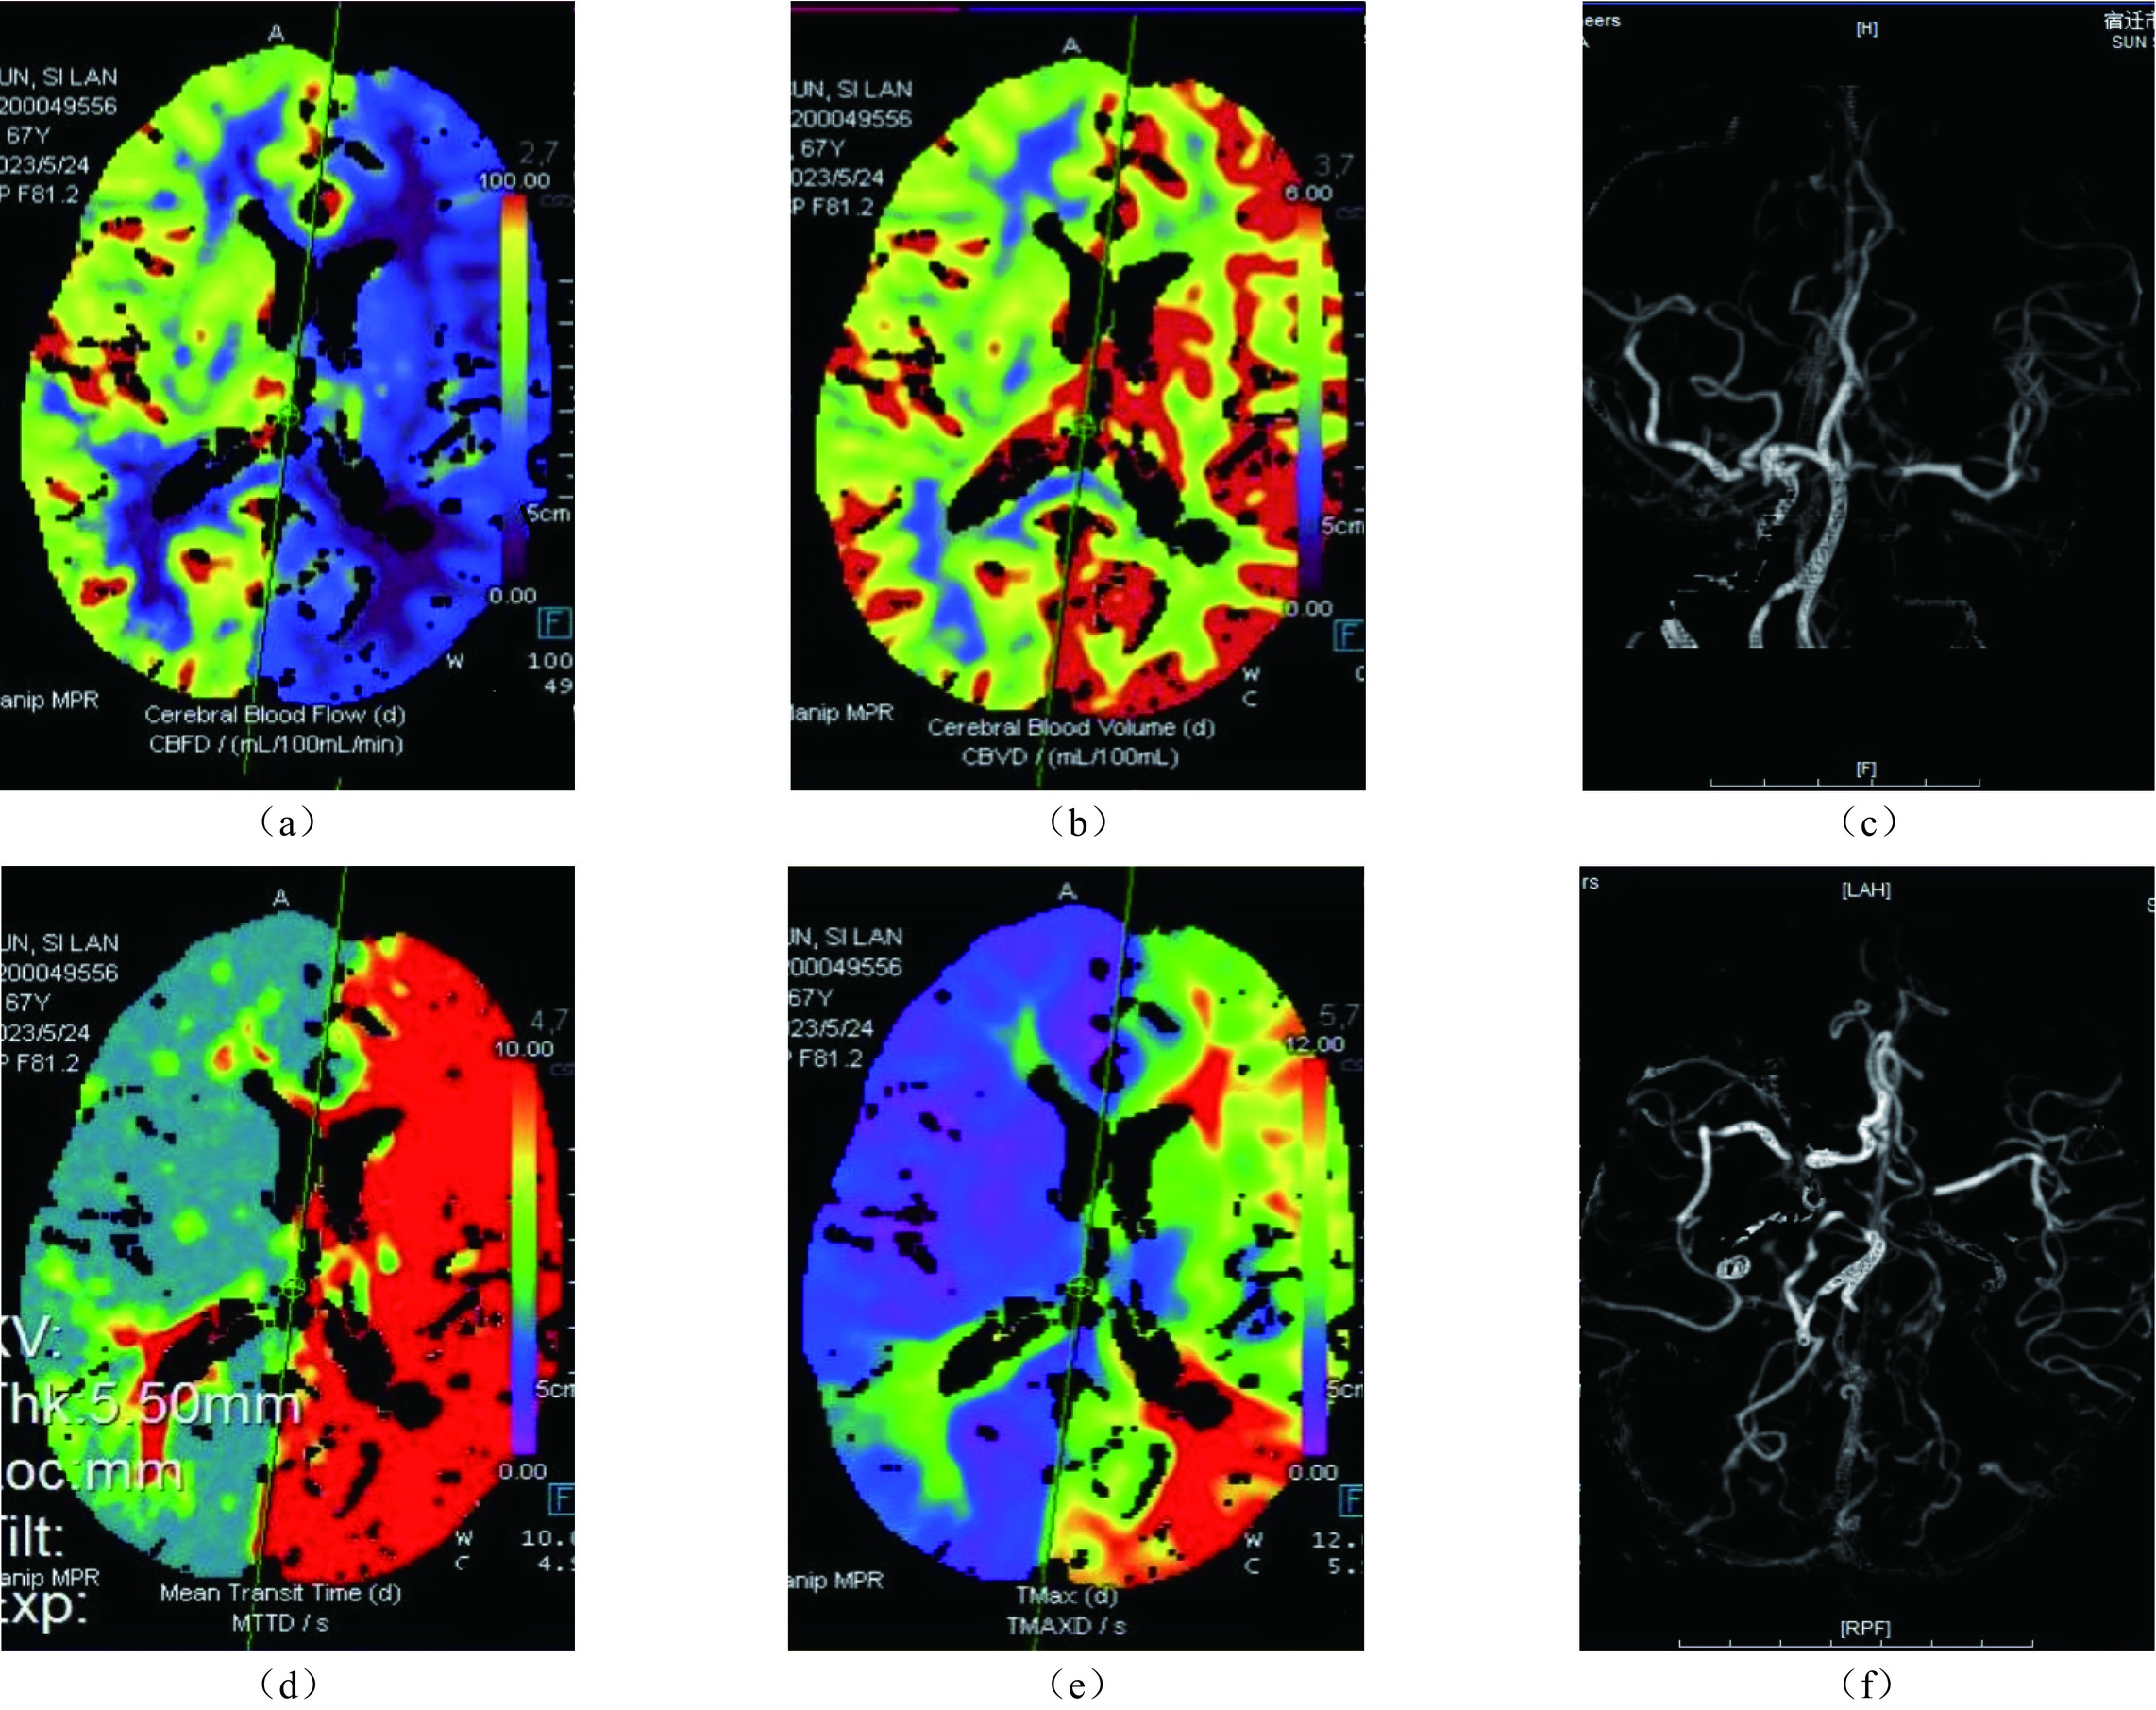

侧支循环不良组CTP参数中CBV、CBF均小于侧支循环良好组,MTT长于侧支循环良好组。见表2。侧支循环不良患者典型病例图像见图1。

表 2 不同侧支循环状态患者CTP参数比较($ \bar{x} \pm s $ )Table 2. Comparison of CTP parameters in patients with different collateral circulation states ($ \bar{x} \pm s $ )组别 例数 CBV(mL/100 g) CBF(mL/100 g/min) MTT(s) 侧支循环不良组 43 2.31±0.92 24.57±5.88 5.15±1.19 侧支循环良好组 49 3.93±1.15 36.27±9.22 3.87±0.86 t 7.498 7.340 5.877 P <0.001 <0.001 <0.001 患者,女性,67岁,侧支循环不良。突发言语不利伴右侧肢体乏力约6 h,急诊绿色通道入院,CTP显示梗死核心区及缺血半暗带区分布范围及体积大小,梗死核心区体积7.78 cm3,缺血半暗带区体积235.74 cm3。1A、1B分别为CBF、CBV图,提示左侧相应区域灌注减低。1D、1E显示MTT、TMAX时间延长。1C、1F为CTA血管图,提示侧支循环不良。